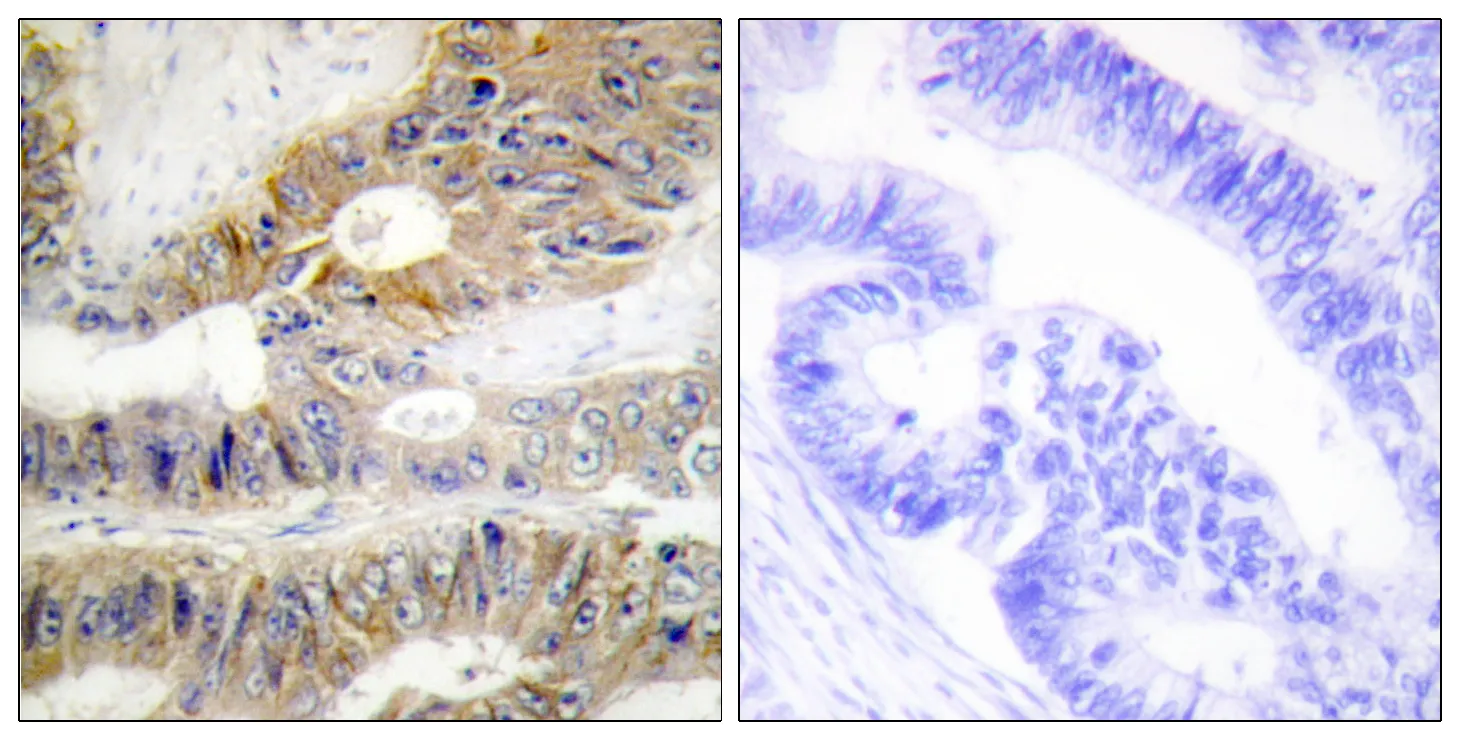

DcR3 Rabbit Polyclonal Antibody

Cat: APRab09848

Size1:50μl Price1:$118

Size2:100μl Price2:$220

Size3:500μl Price3:$980

Size2:100μl Price2:$220

Size3:500μl Price3:$980